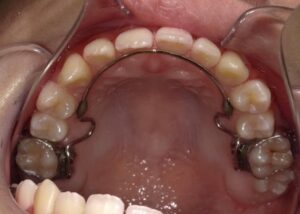

上顎

- After